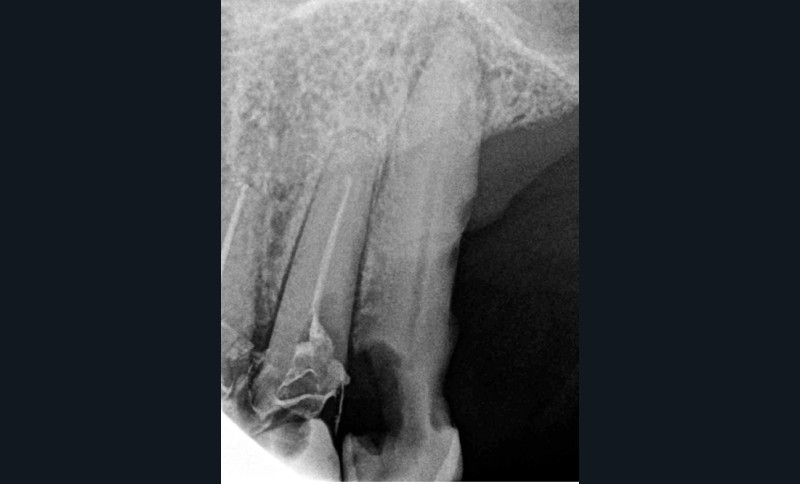

– carie radiculaire importante à la 21 ;

– 22 est couronnée et présente également une carie radiculaire ;

– 13 est très cariée et présente une alvéolyse dépassant le tiers apical de la racine.